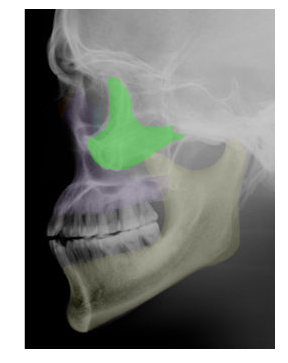

| ZYGOMATIC |

in green,  | PARIETAL |